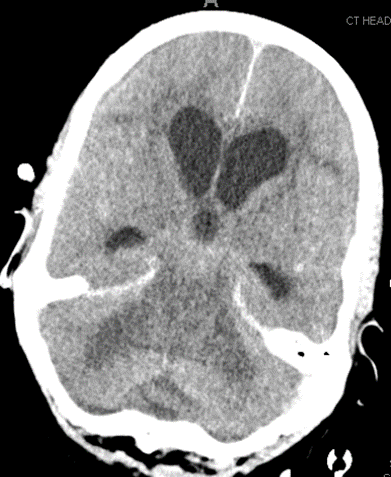

4/ All the ventricles are enlarged. There is some degree of transependymal flow with sulcal effacement, so unlikely this is NPH. Most likely communicating π§ π§. But why?

5/ Remember a colloid cyst will give you obstructive π§ π§. Patient without history of cancer, but cannot rule out, so vast differential. Do you LP?